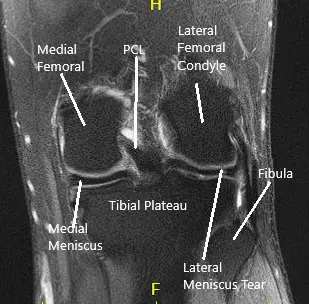

La resonancia magnética de la rodilla izquierda sugirió un desgarro meniscal lateral… Hubo una pérdida leve de cartílago de grosor parcial a lo largo del surco troclear central y en el compartimento lateral.

Resonancia magnética de rodilla en secciones coronal y sagital